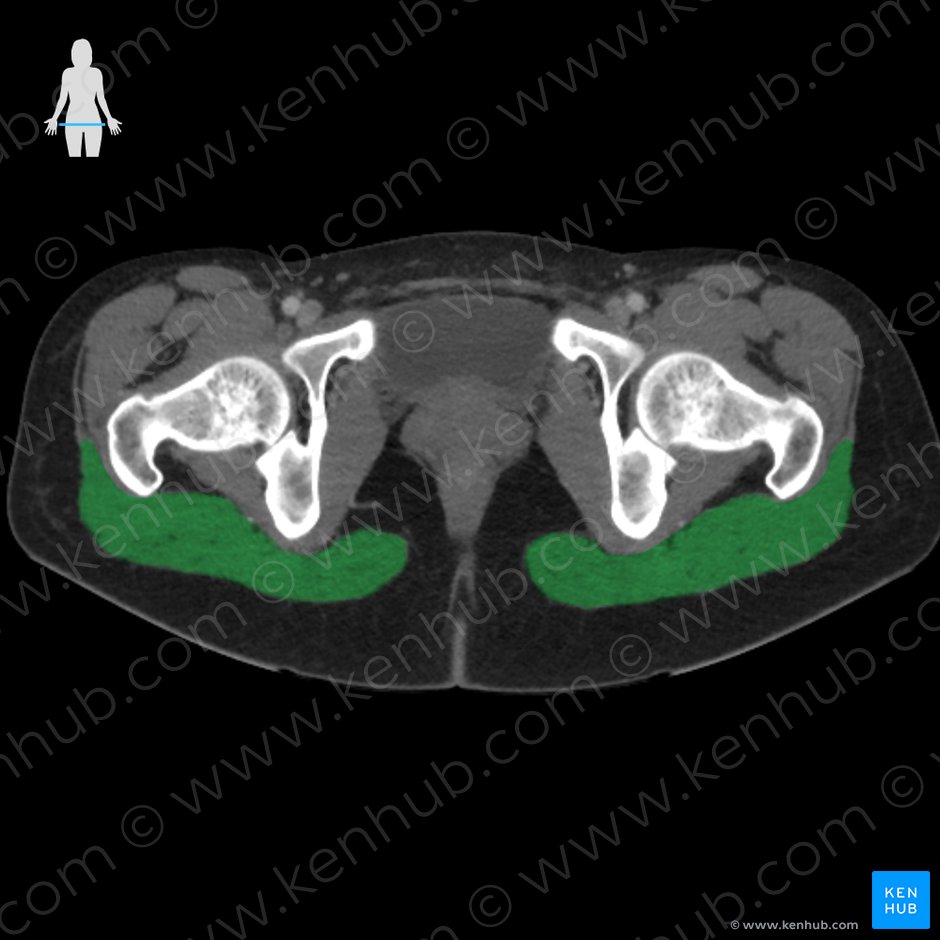

위치상 소둔근과의 차이를 구분하기 어렵기 때문에

치료적 접근 시 뼈까지 깊게 자극하여 두 근육을 모두 풀어줍니다.(혈종에 주의)